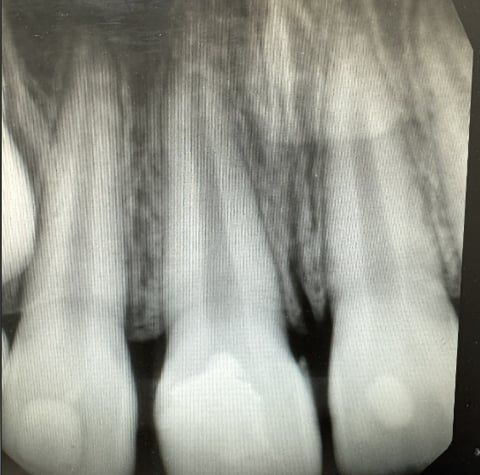

Coming out of school and residency, I was taught and practiced restoring these cases “free hand.” While I had no problem achieving the result I wanted, I’m sure all dentists can relate to how time-consuming Class IV’s can be. While other products and techniques exist with varying cost and complexity, I find that the best way to predictably, effectively and efficiently treat is with strip crowns.

As a pediatric dentist, I routinely place strip crowns on primary incisors. Through repetition, I naturally improved my esthetic skills and results over time. For any general dentist reading who may not be as familiar, it basically involves filling uncured restorative material into a tooth-shaped plastic mold, placing and curing it onto the tooth, and then removing the mold to leave behind a cured restoration. While for carious primary teeth we typically prefer glass ionomer for strip crowns (in vogue among pediatric dentists), for adult teeth we certainly prefer composite for its superior physical properties.

To break it down step-by-step, the technique involves:

- Bevel/etch/bond (business as usual)

a. (Tip: Etch for a full 30 seconds. Surface area is your friend for retention) - “Free hand” a small layer of OMNICHROMA BLOCKER to restore general shape

- Choose the correct size strip crown (my preferred brand for pediatrics and adults is Nowak) and trim to incisogingival length with scissors

- Fill the strip crown with OMNICHROMA Flow BULK

a. (Tip: pack starting from the incisal edge to prevent voids)

- Cure both sides

- Use a scaler to flick off the cured excess

- Remove (or strip–hence the name) the plastic mold off with an explorer

- Cure one more time for good luck

- If necessary, adjust occlusion and use a fine finishing bur or finishing strips to polish

That’s it, you’re done. Better and faster. The average treatment time is less than 10 minutes. You’ll usually find the margins seamless and the finishing flawless. I also find that because the restoration is basically full coverage, the retention is a lot stronger than free hand.